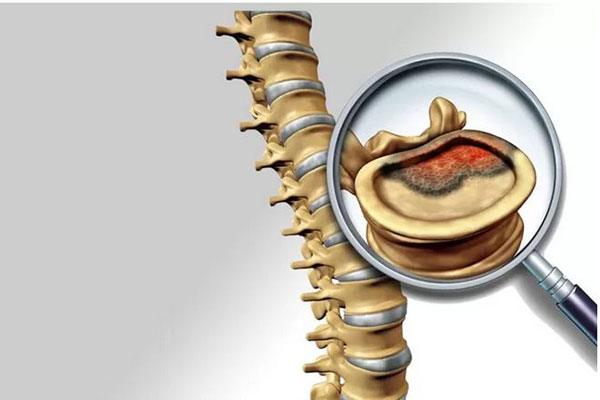

کوردوما

کوردوما یک نوع سرطان استخوان بسیار نادر و با رشد کند است.کوردوما از نوتوکورد رشد می کند، که بافت اولیه نخاع را در نوزادی که در رحم رشد می کند، تشکیل می دهد.در طول رشد، نوتوکورد با استخوان جایگزین می شود.

اما گاهی اوقات، نواحی کوچک نوتوکورد ممکن است در بزرگسالان باقی بماند.حدود 35 از 100 کوردوما (35%) در قاعده جمجمه و 50 از 100 (50%) در استخوان (ساکروم) بین استخوان های لگن رشد میکنند.بقیه در استخوان های ستون فقرات رشد می کنند.